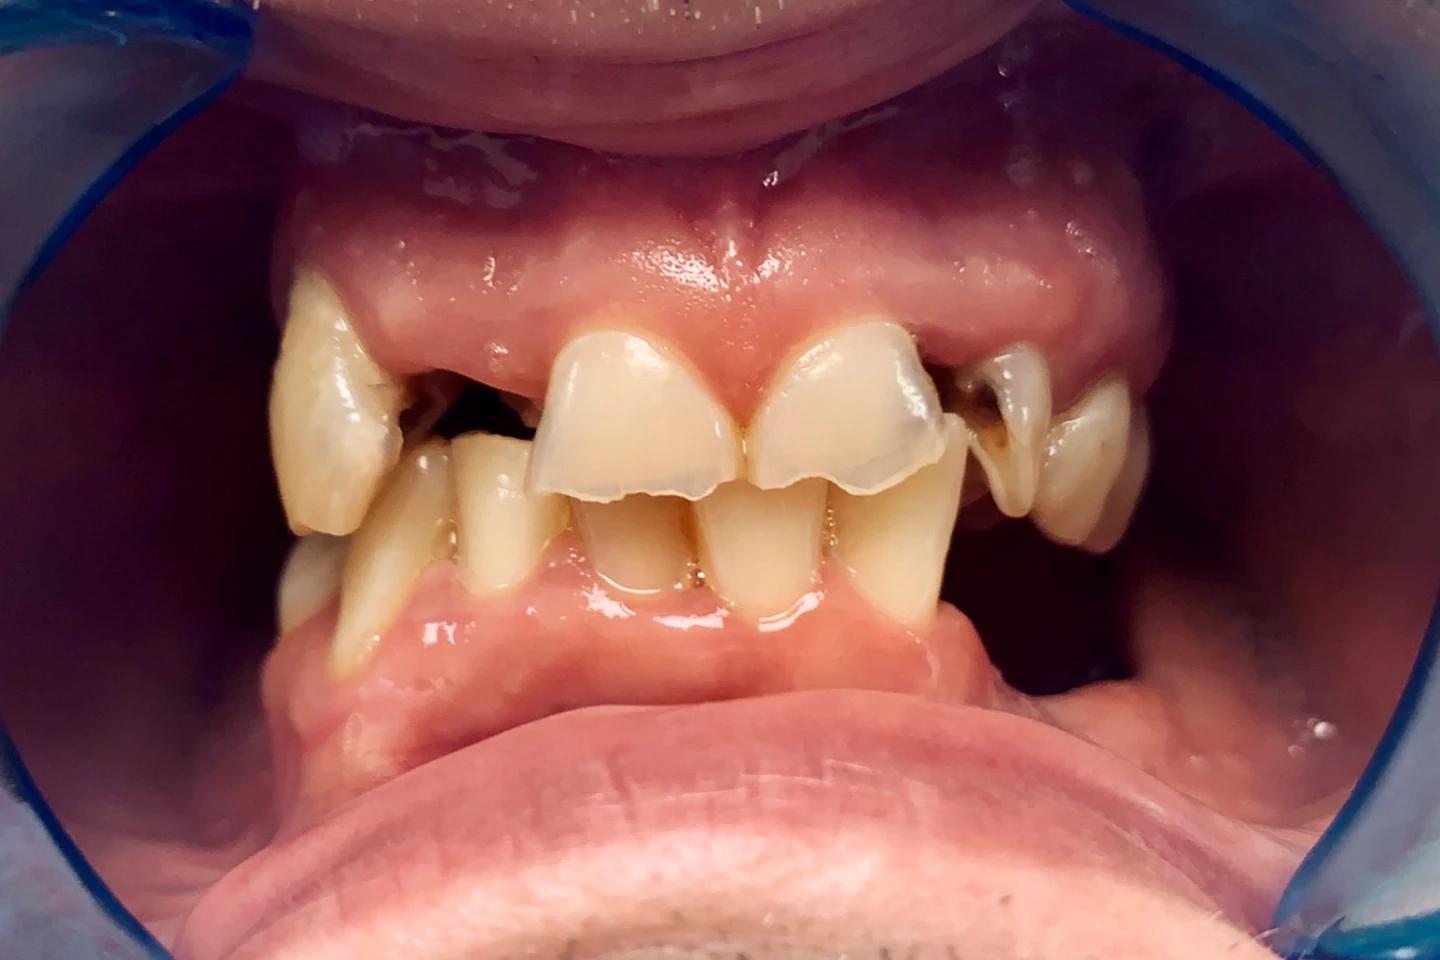

Zubi pre i posle

Osmeh i oblik zuba slike - pre i posle

Stomatološka ordinacija Marco Dental Tourism svakodnevno stvara neverovatne transformacije osmeha. Pogledajte galeriju naših radova i uverite se u moć stomatologije!

Fasete za zube - pre i posle

- Korigujte manje nepravilnosti i postignite blistav osmeh uz pomoć faseta. Pogledajte kako fasete mogu da transformišu vaš osmeh u samo nekoliko poseta.